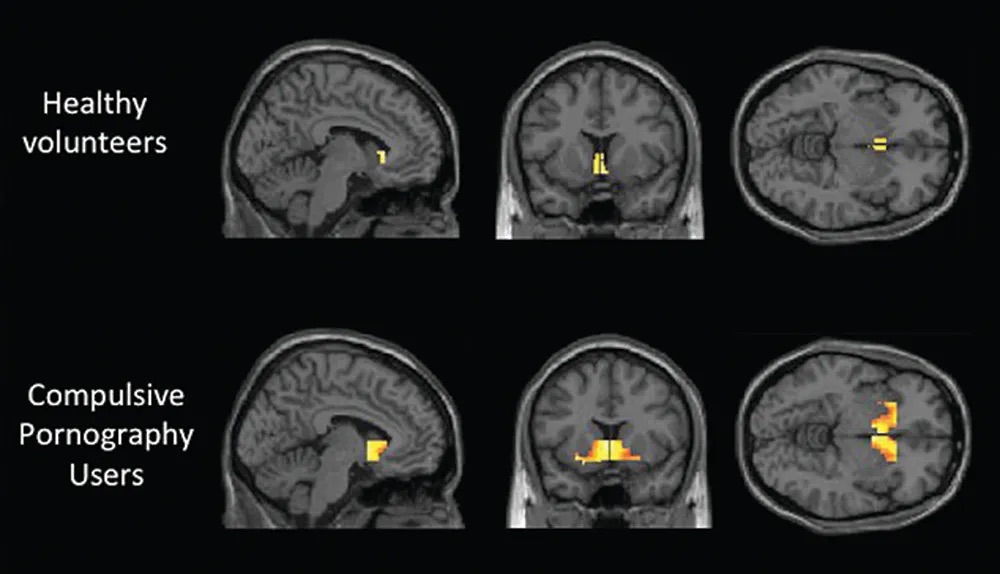

The yellow/orange regions are areas of increased neural activation during a stimulus - exposure to erotic cues.